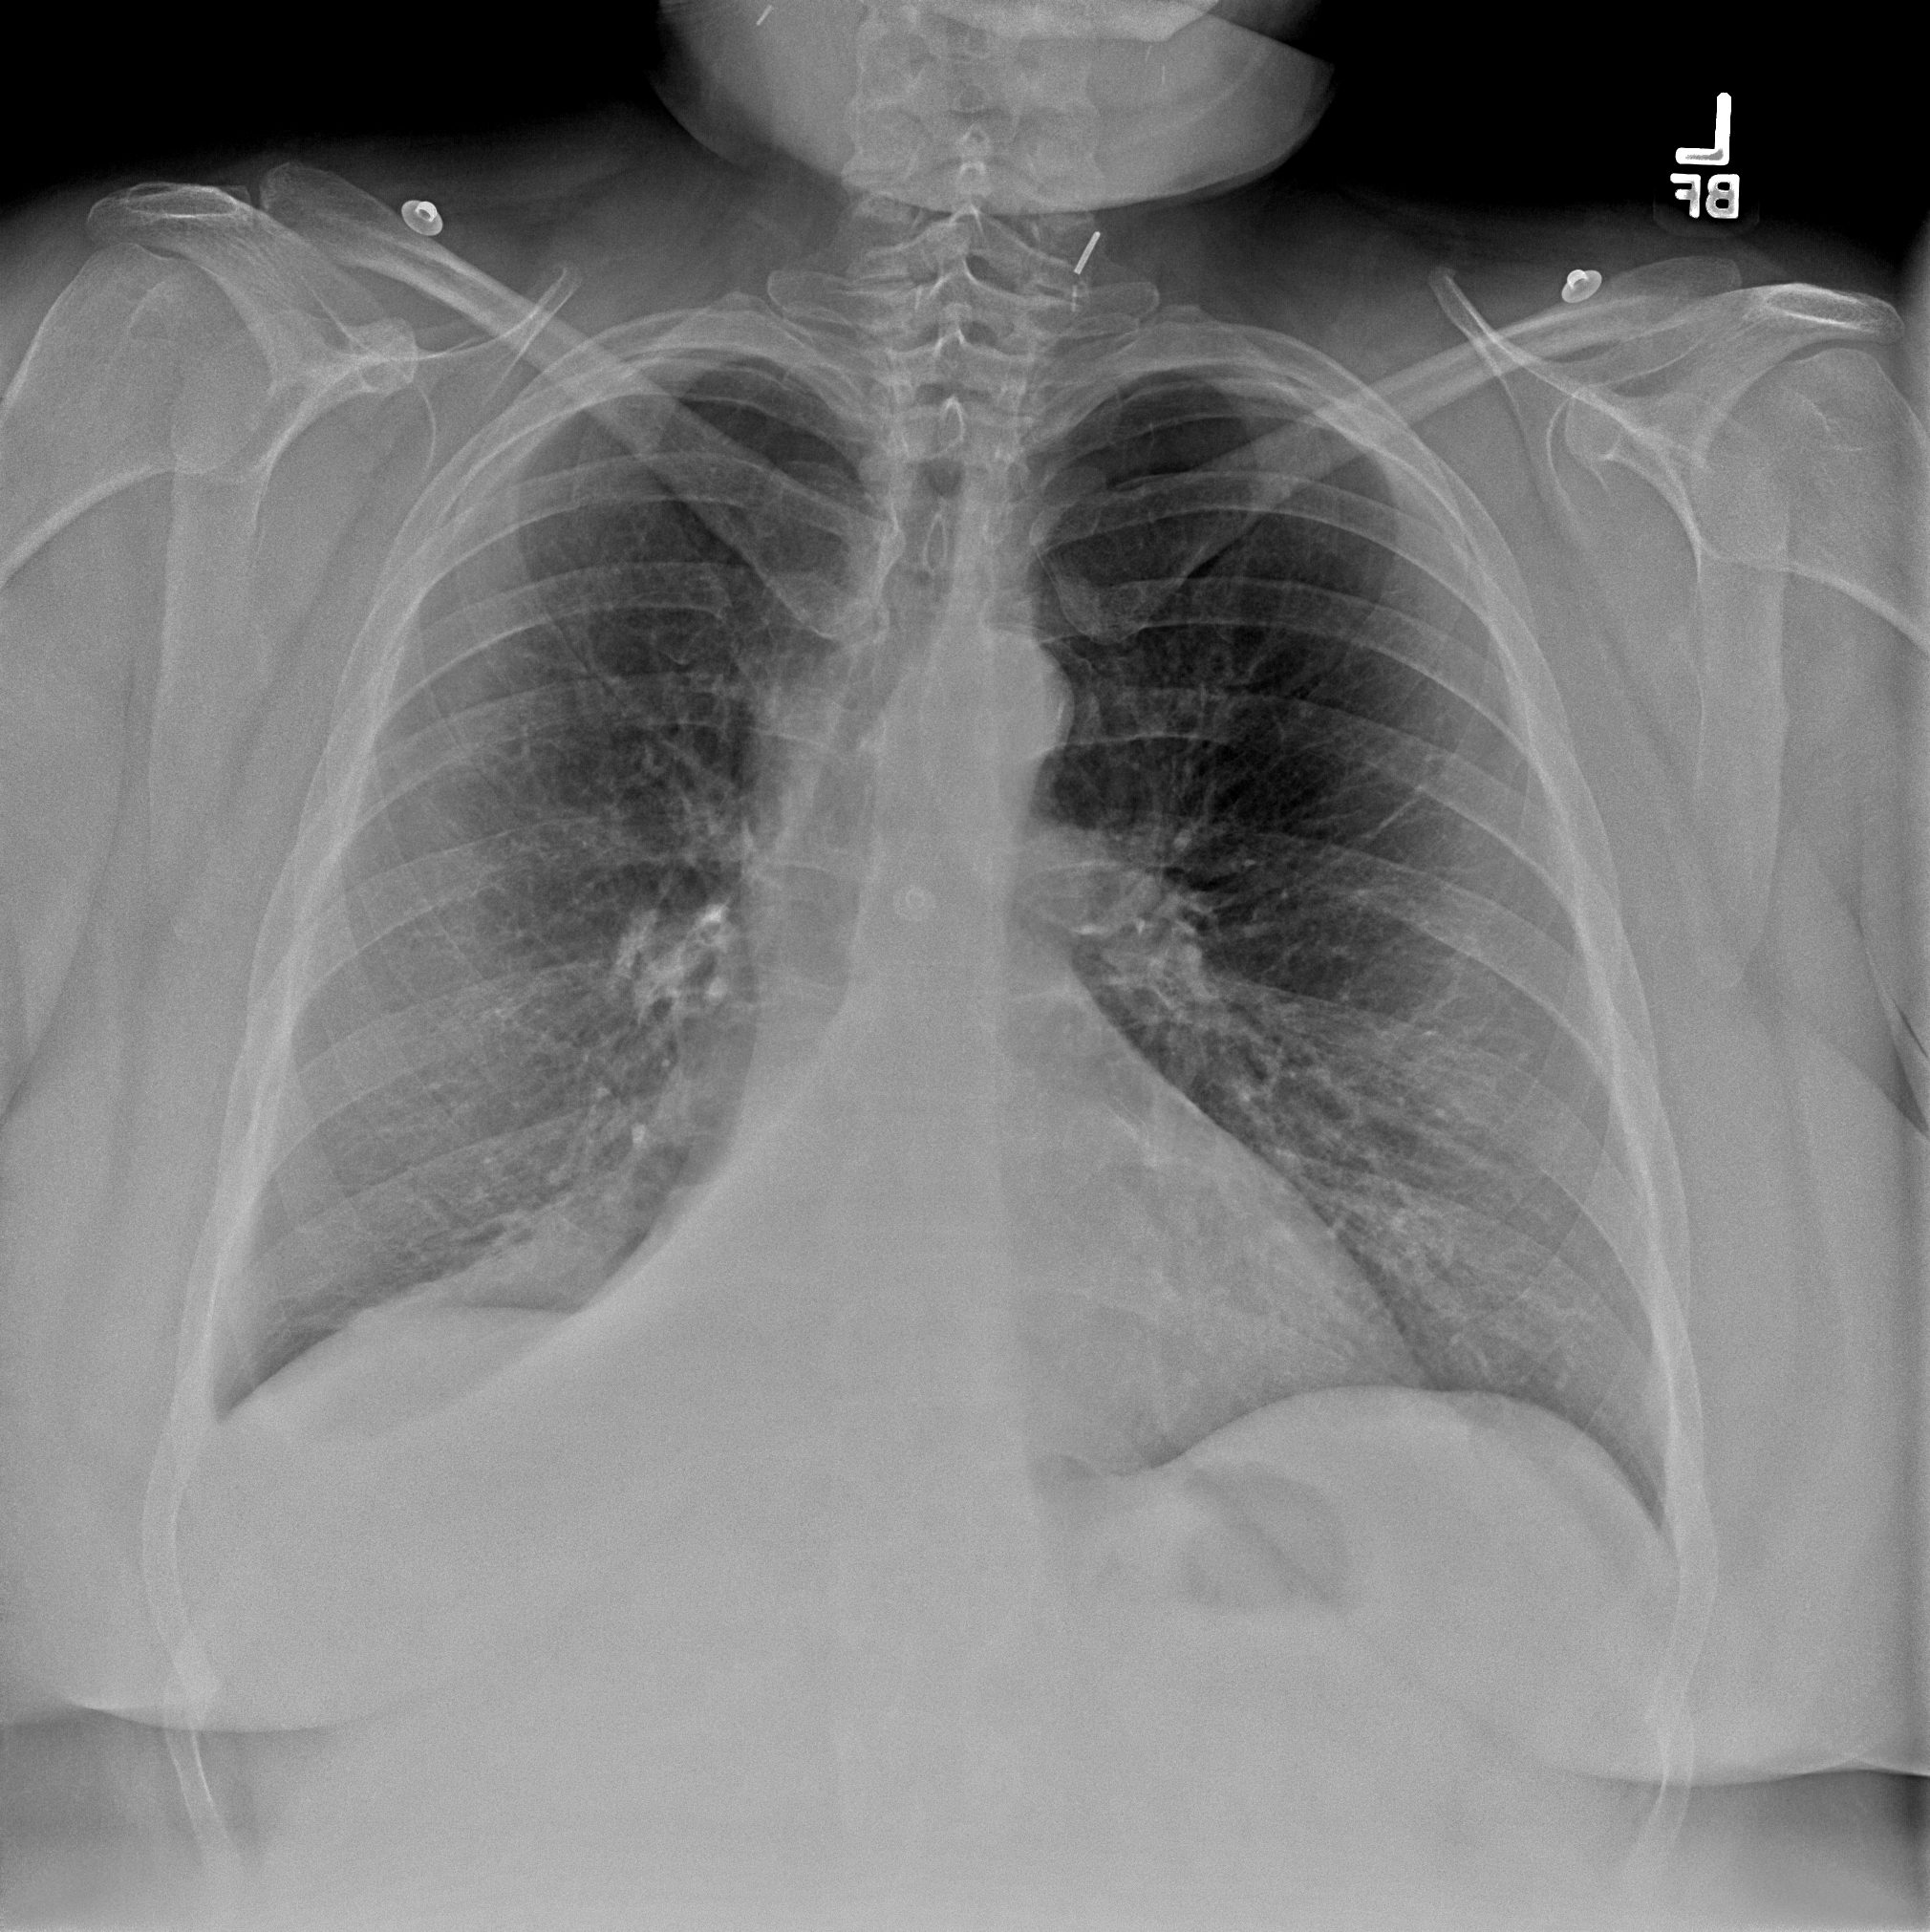

Practice Cases